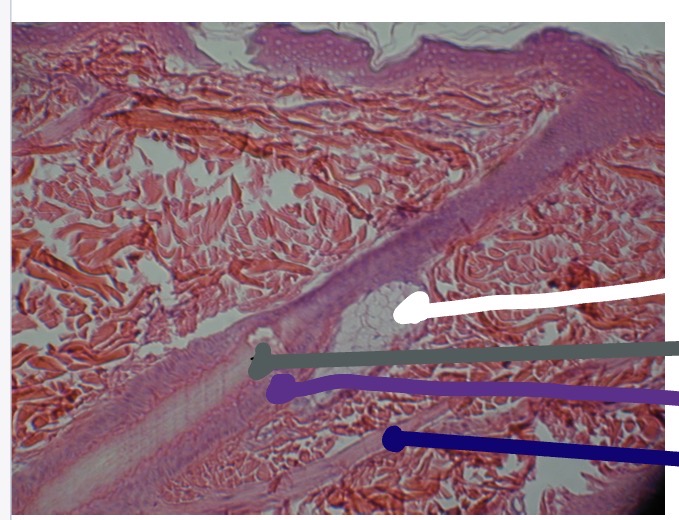

<p>What’s the white line in this photo</p>

Sebaceous Gland

<p>What’s the dark purple line in this photo</p>

Hair Shaft

<p>What’s the light purple line in this photo</p>

Apocrine Sweat Gland

<p>What’s the black line in this photo</p>

Sweat Pore

<p>What’s the red line in this photo</p>

Hair Follicle

<p>What’s the blue line in this photo</p>

Hair Root

<p>What’s the green line in this photo</p>

Arrector Pili Muscle

<p>What’s the dark blue line in this photo</p>

Hair Papilla

<p>What is the dark green line </p>

Eccrine Sweat Gland